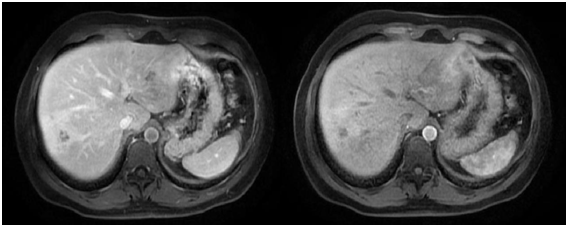

Figure 1 Abdominal CT scan with contrast in arterial and venous phases showing the presence of a hypodense image in the right hepatic lobule (RHL) compromising segments VI and VII suggesting subcpasular haematoma.

In our patients, each one has a different image as a result of the varying diagnostic approach (abdominal ultrasound, CT scan or MRI scan). The patient in Case no.1 had two imaging examinations: abdominal ultrasound and CT scan. The abdominal ultrasound indicated the presence of a hyperechogenic area in right hepatic lobule (RHL) that compromised segments VI and VII. The CT scan showed the presence of a hipodense image of well defined borders at the level of segments VI and VII (see Fig. 1) that could correspond to a hepatic abscess. The patient in Case no. 2 had three imaging examinations: abdominal ultrasound, CT scan and MRI scan. The abdominal ultrasound showed the presence of hepatic nodules in segments VI and VII. The abdominal CT scan reported hipodense nodules in segments VI, VII and VIII with contrast medium enhancement at later stages, as well as hepatomegaly. The MRI scan demonstrated images suggestive of hepatic micro abscesses (Figure 2). The patient in Case no. 3 had two imaging examinations: abdominal ultrasound and abdominal CT scan. The abdominal ultrasound revealed hepatomegaly and fusiform and ovoid images on the left hepatic lobule (LHL) and dilatation of the biliary duct. The abdominal CT scan demonstrated multiple hipodense, heterogeneous images, with a diffuse distribution (Figure 3). Analyzing the findings of the imaging examinations of our three patients, despite the multiple formats of presentation, there is agreement of the majority of the findings with those reported by others elsewhere, although the imaging examinations did not permit us to make a definitive diagnosis in a nosological entity sense, in a certain manner the imaging examinations in conjunction with the clinical pictures and the blood analysis permitted us to put aside the possibilities of other etiologies, particularly neoplastic or infectious (hepatic abscesses and other parasitosis, such as hydatidosis).